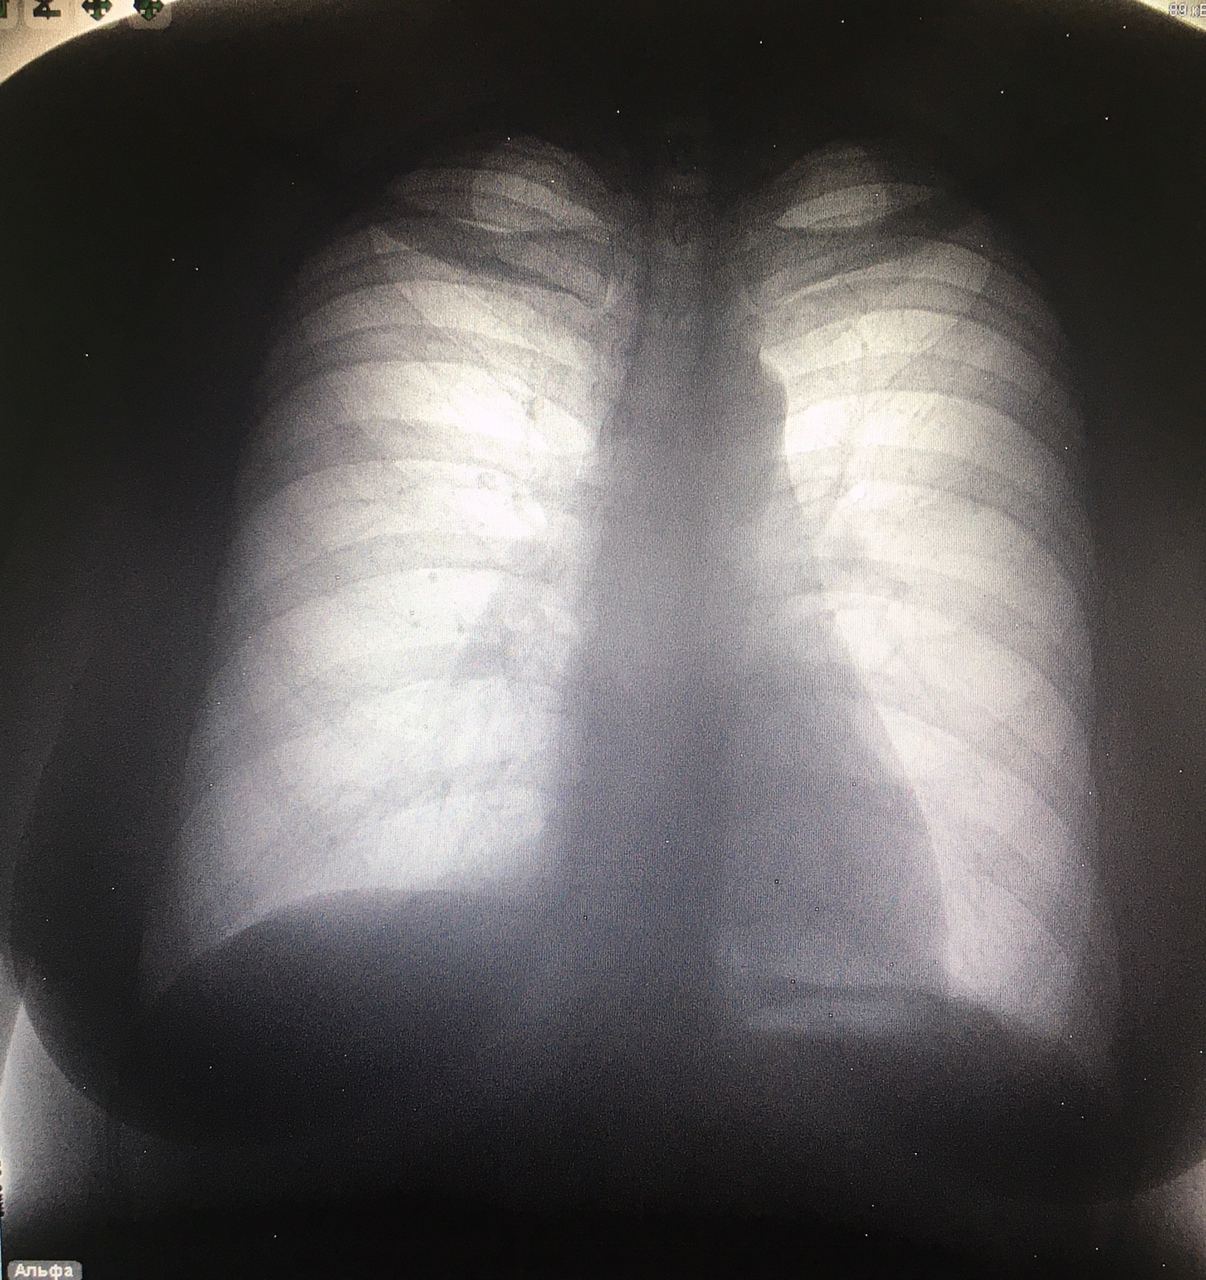

У вас тоже Зернит?

Что-то мерекается

И мне

Дообследование б

Липома ?

Киста?

Хотя меня напрягает обызвествление внутри

Р

Nikita Levin

Именно участки обызвествления вызывают вопросы

Липома смело пишите